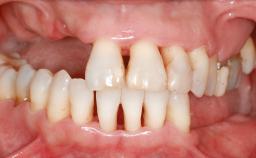

A 47-year-old Caucasian woman with a single-tooth edentulous space at the site of the left maxillary canine was referred for treatment. She had undergone traumatic extraction of this impacted canine several months before referral. Her chief complaint was the dissatisfying appearance of her smile. The patient desired a stable and esthetic rehabilitation of the site. Her dental history showed no evidence of periodontal disease or bruxism. She had no systemic diseases, was not taking any medications, and did not smoke. The extraoral examination revealed a high lip line and an inadequate soft-tissue volume at the defective canine site. Large black triangles were visible between the canine and its adjacent teeth.